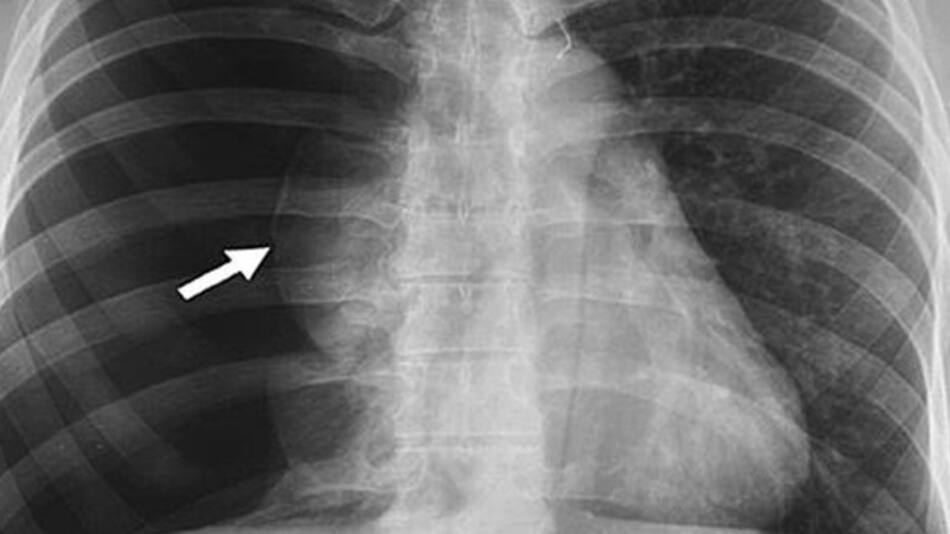

La Enfermedad Pulmonar Obstructiva Crónica (EPOC), es una patología del pulmón que dificulta la respiración, lo que provoca falta de aire. Otros de sus síntomas más característicos son tos, opresión en el pecho y silbidos al respirar. La disminución de la capacidad respiratoria avanza lentamente con el paso de los años y ocasiona un deterioro considerable en la calidad de vida de las personas afectadas.